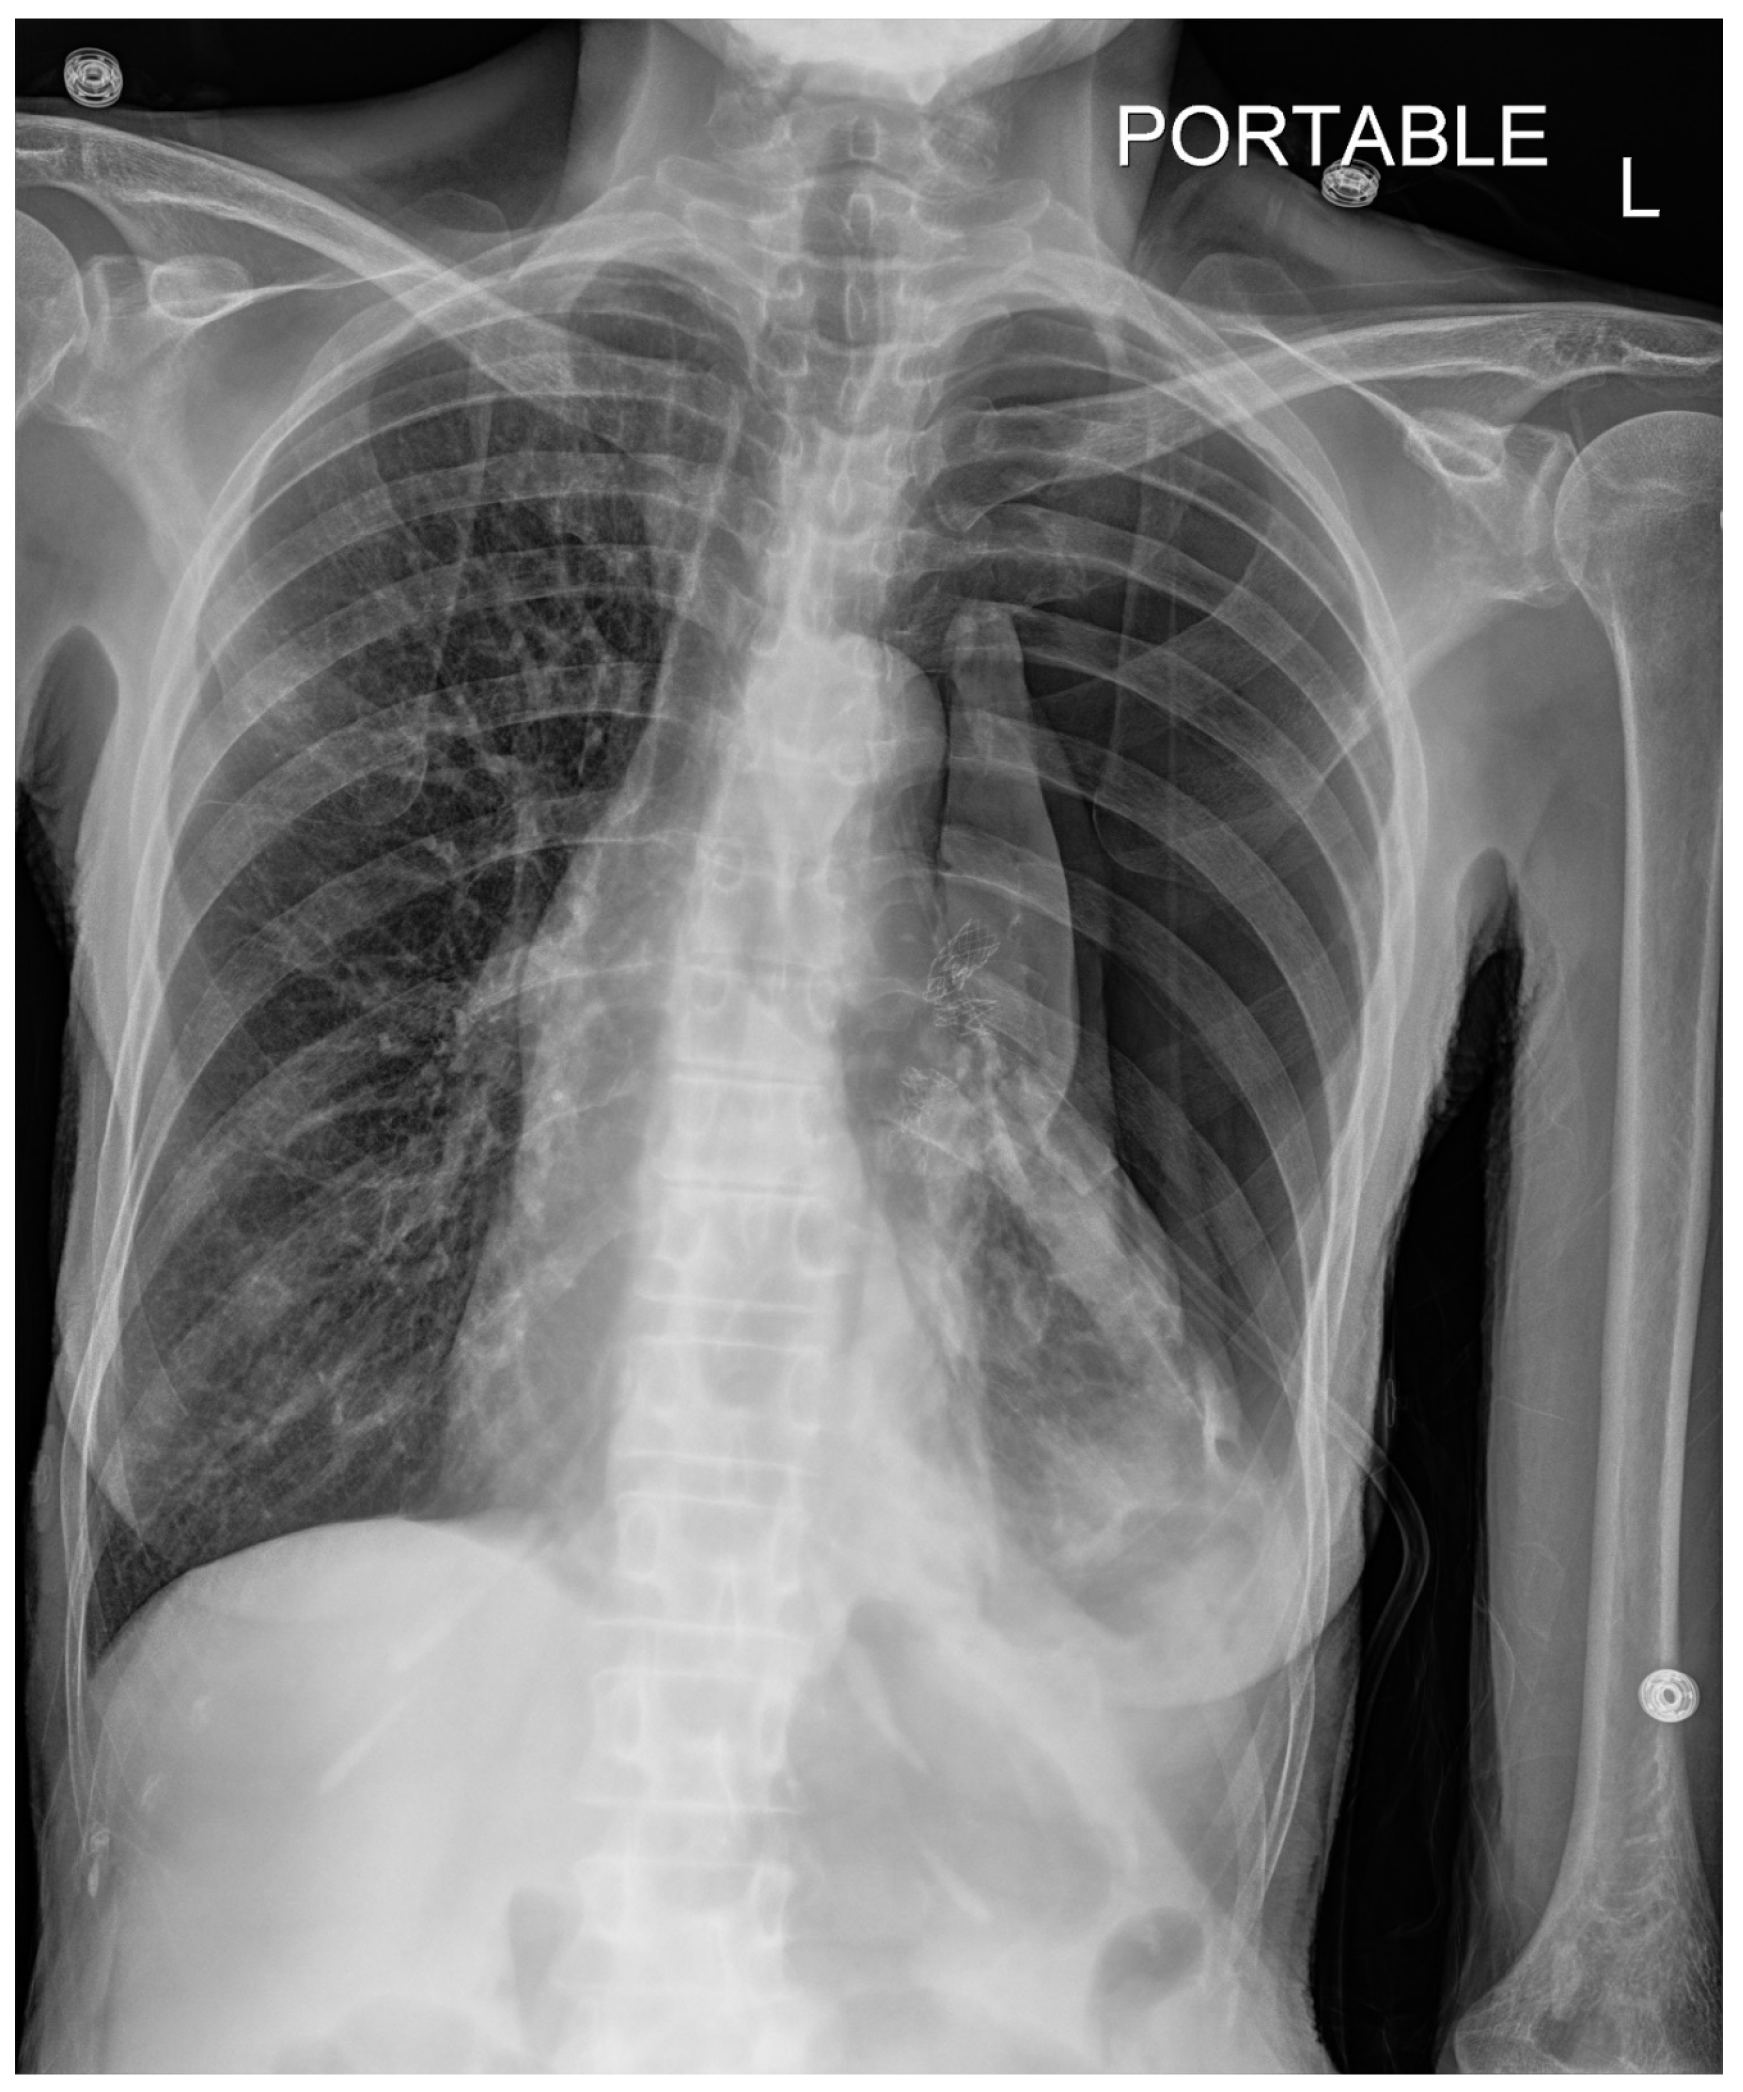

Pneumothorax (Figure 1, Figure 2, Figure 3 and Figure 4) developing after the placement of endobronchial valve (Figure 5) is usually managed by pulmonologists; however, anesthesia providers should be aware. Dijk et al. published their revised expert statement that addresses the issue of pneumothorax extensively [53]. The development of pneumothorax is related to compensatory expansion of the untreated ipsilateral lobe. Such an expansion might result in the rupture of blebs, bullae, and fragile lung tissue [54]. The bronchopleural fistula that develops leads to air leak, which can get worse and become clinically significant very quickly. Pneumothorax can also develop in the vacuum created by therapeutic lung collapse (pneumothorax ex vacuo). The air enters the potential space from the ambient tissues and blood [55]. As there is no bronchoalveolar fistula in this situation, a chest drain is not necessary, and the pneumothorax will spontaneously resolve over time.

Pneumothorax can develop in the immediate postoperative period, in the post anesthesia care unit or within the first 3 days [46,56]. Valipou et al. published their management algorithm for pneumothorax [57]. Nearly 80% of them happen in the first 48 h, 10% in about 3-5 days, and 10% after day 6 [58,59]. Both anesthesia providers and bronchoscopists should be particularly vigilant about the development of tension pneumothorax. Certain post procedural protocols- (cough suppression, strict bed rest, not letting to elevate the arm above shoulders) are employed at Jefferson to minimize the pneumothorax risk. Most pneumothoraces ‘s are treated conservatively with serial imaging. some may require chest tubes and rarely valve removal.

Figure 4. CXR Left upper lobe volume loss (day 2). Moderate left pleural effusion compatible with hemothorax (which was seen on CTscan). Stable cardiac silhouette. Left apical chest tube. Left hilar endobronchial valves.